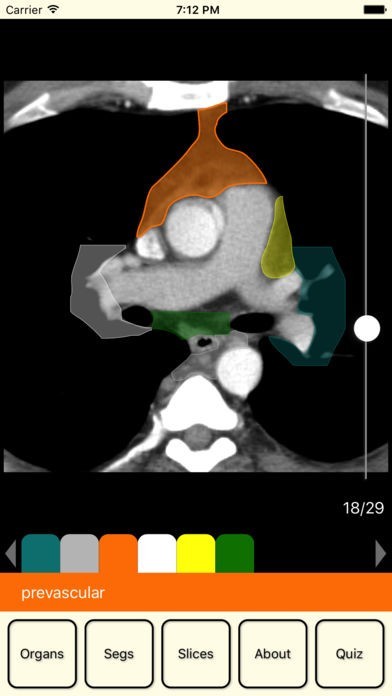

This application is a helper for students and doctors and can not be used to diagnose.

Content of this application has been provided by a certified specialist and practice radiologist Vitalii Rogalskyi.

Browse an organ image slice by slice to learn it segmental structure. Zoom this image for a good view. Test yourself in the quiz.